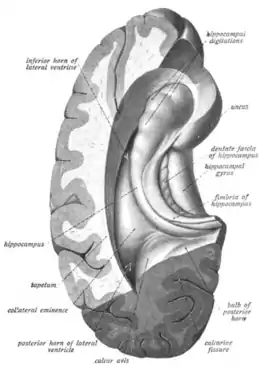

The hippocampus can be seen as a ridge of gray matter tissue, elevating from the floor of each lateral ventricle in the region of the inferior or temporal horn.[17][18] This ridge can also be seen as an inward fold of the archicortex into the medial temporal lobe.[19] The hippocampus can only be seen in dissections as it is concealed by the parahippocampal gyrus.[19][20] The cortex thins from six layers to the three or four layers that make up the hippocampus.[21]

The hippocampus, including the dentate gyrus, has the shape of a curved tube, which has been compared to a seahorse, and to a horn of a ram, which after the ancient Egyptian god often portrayed as such takes the name cornu Ammonis. Its abbreviation CA is used in naming the hippocampal subfields CA1, CA2, CA3, and CA4.[20] It can be distinguished as an area where the cortex narrows into a single layer of densely packed pyramidal neurons, which curl into a tight U shape. One edge of the "U," – CA4, is embedded into the backward-facing, flexed dentate gyrus. The hippocampus is described as having an anterior and posterior part (in primates) or a ventral and dorsal part in other animals. Both parts are of similar composition but belong to different neural circuits.[22] In the rat, the two hippocampi resemble a pair of bananas, joined at the stems by the commissure of fornix (also called the hippocampal commissure). In primates, the part of the hippocampus at the bottom, near the base of the temporal lobe, is much broader than the part at the top. This means that in cross-section the hippocampus can show a number of different shapes, depending on the angle and location of the cut.

In a cross-section of the hippocampus, including the dentate gyrus, several layers will be shown. The dentate gyrus has three layers of cells (or four if the hilus is included). The layers are from the outer in – the molecular layer, the inner molecular layer, the granular layer, and the hilus. The CA3 in the hippocampus proper has the following cell layers known as strata: lacunosum-moleculare, radiatum, lucidum, pyramidal, and oriens. CA2 and CA1 also have these layers except the lucidum stratum.